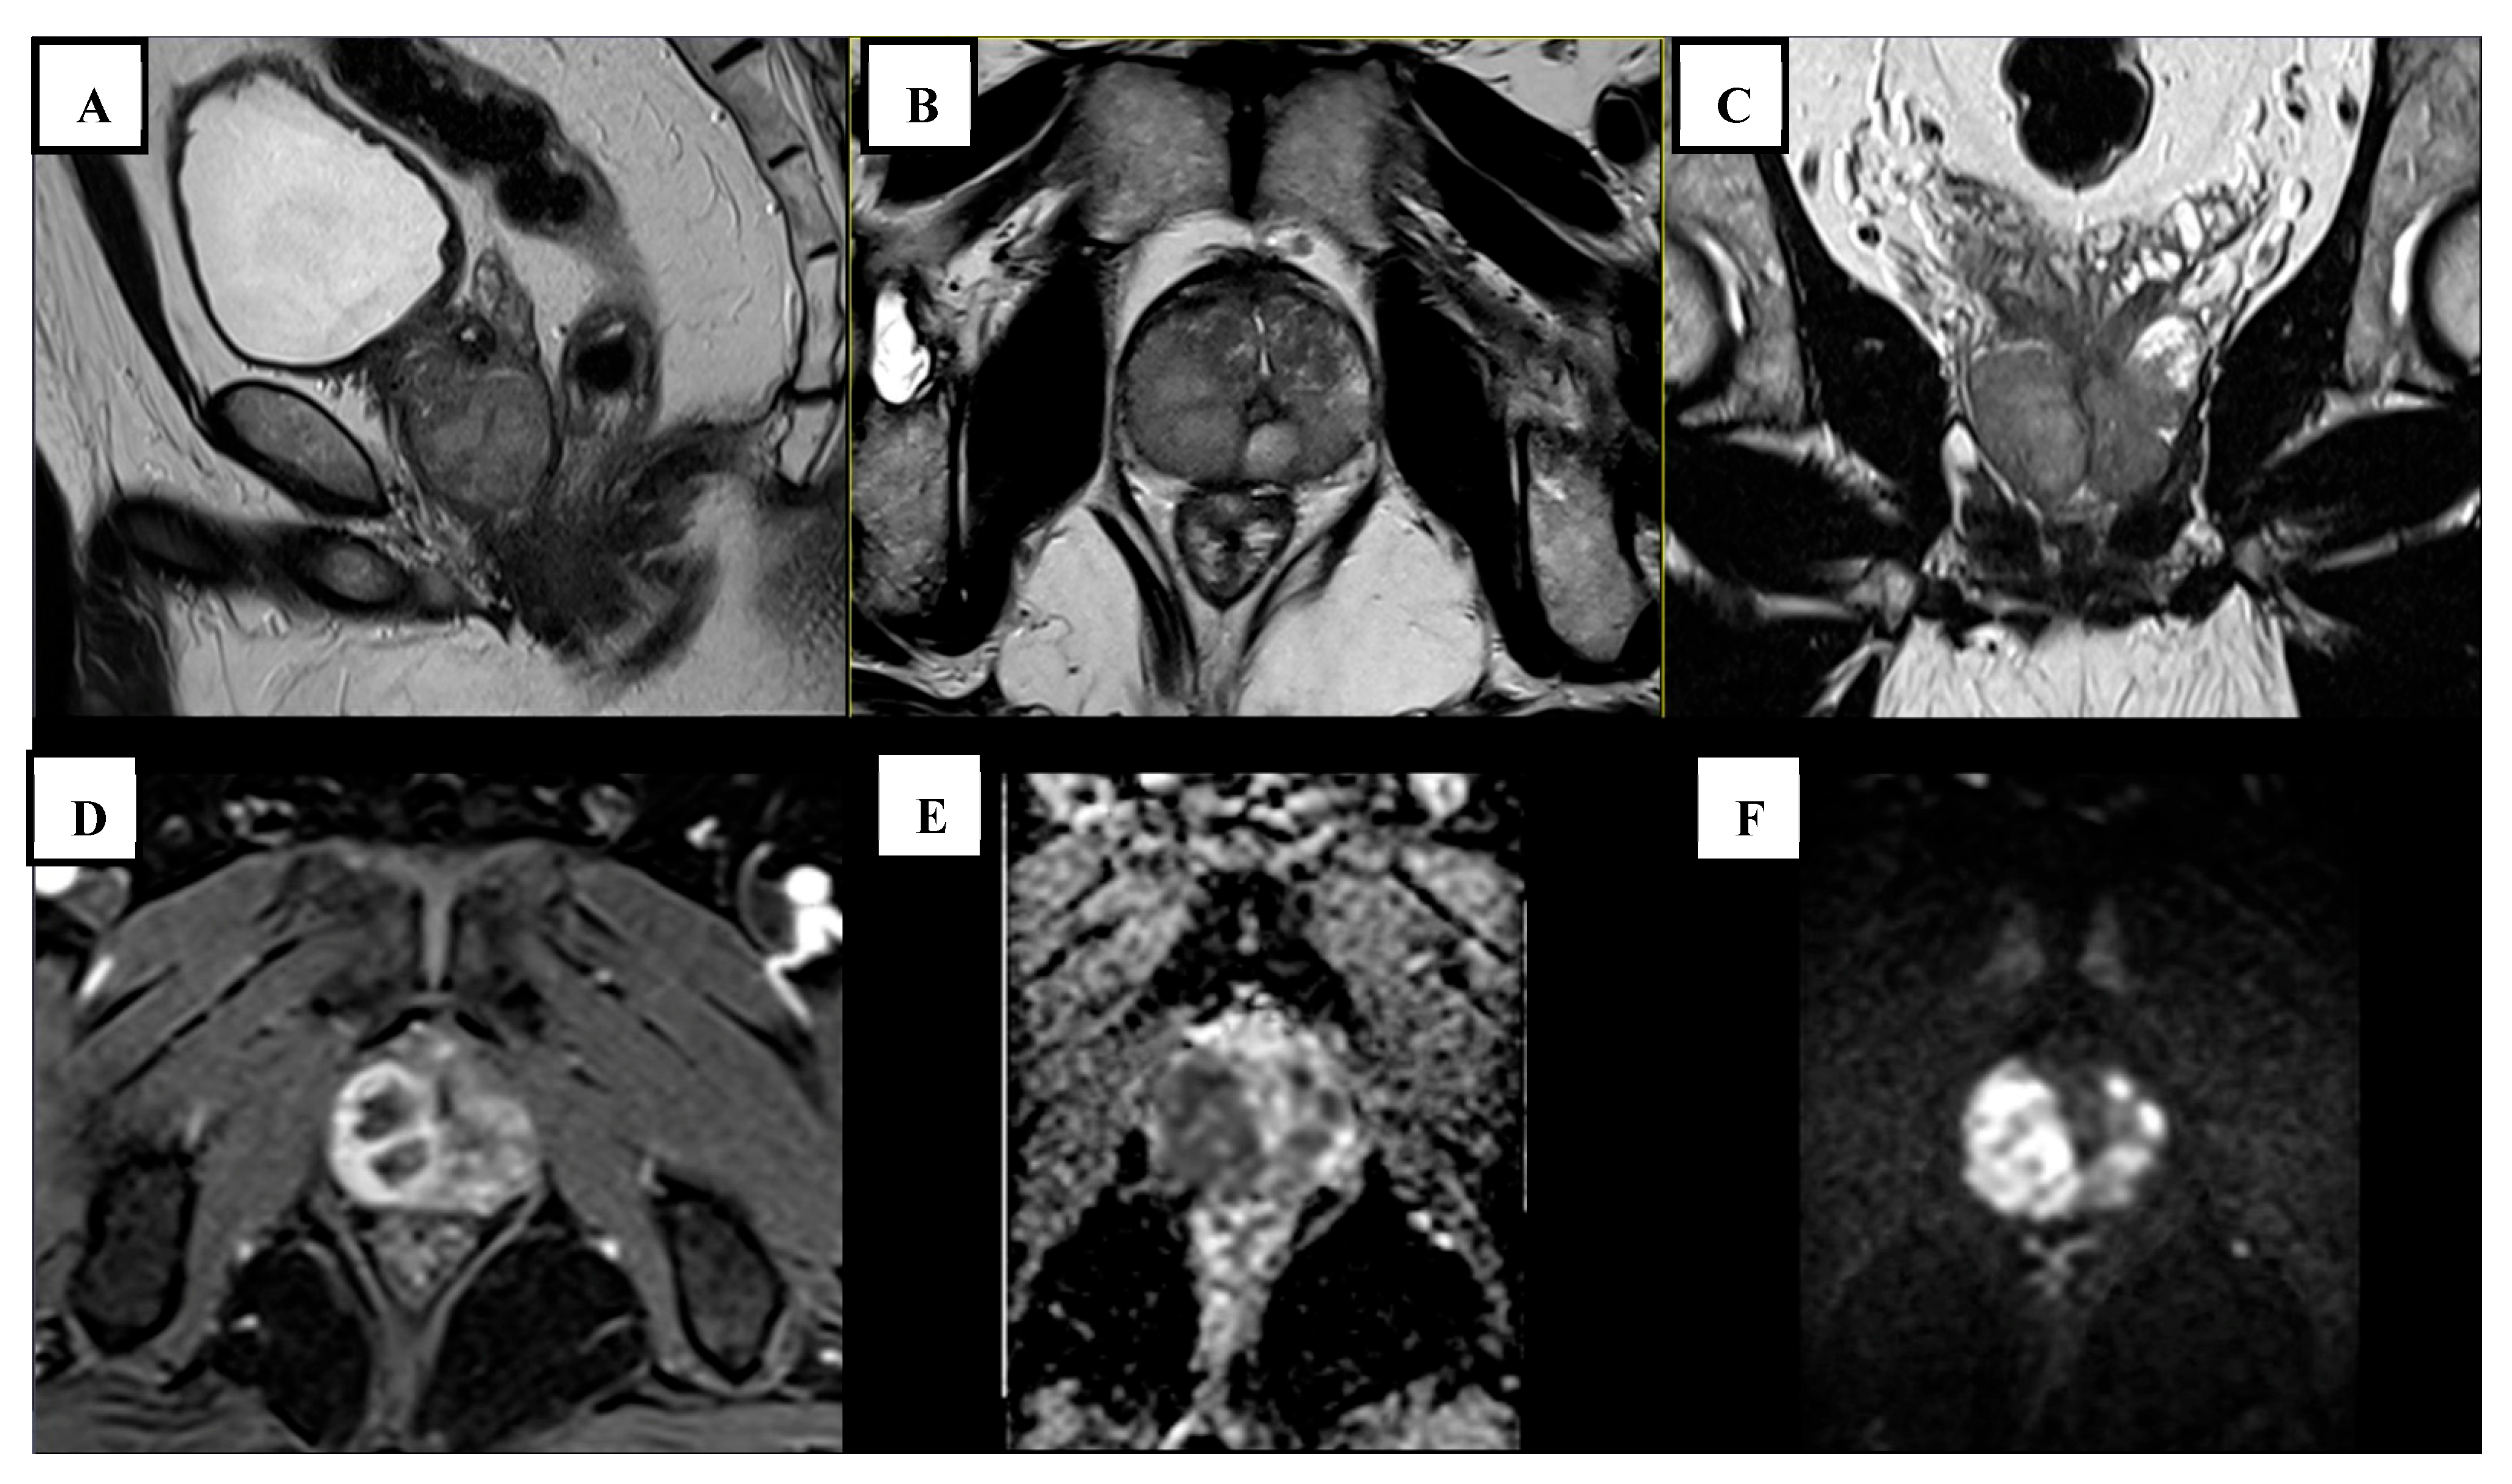

| Legesse (2024) [18] | 69 | None | 1768 | Yes | 5 | The transitional zone appeared enlarged with mixed signal intensity on T2WI. A focal hypointense lesion was detected in the right basal and midzone of the prostate, extending into the peripheral zone. This lesion was accompanied by capsular obliteration and extraprostatic extension. It exhibited restricted diffusion on DWI and the ADC. |

| Aslan (2022) [19] | 80 | None | N/A | No | N/A | A poorly defined, low-signal intensity lesion was identified in the left anterolateral peripheral zone on T2WI. The lesion exhibited restricted diffusion and early ring enhancement. |

| Li (2023) [3] | 52 | None | 12.4 | No | N/A | A mass-like abnormal signal shadow was detected in the peripheral zone, appearing isointense on T1WI, slightly hyperintense on fat-suppressed T2WI, and hyperintense on DWI. Additionally, the lesion had invaded the left seminal vesicle gland, while the left peripheral zone exhibited significant heterogeneous enhancement, and pelvic lymph nodes were observed. |

| Fonseca (2018) [17] | 73 | None | 6.54 | No | 2 | A small nodule with abnormal diffusion restriction was detected in the left posterior mid-third of the transition zone. It exhibited intense peripheral post-contrast enhancement with a liquefied center, indicative of a microabscess. |

| Hau (2022) [16] | 62 | None | 4.5 | No | 3 | Multiple lesions were present in the transitional zone and bilateral peripheral zone of the prostate. On T2-weighted imaging, the entire gland’s parenchyma appeared slightly elevated with irregular signals. It showed no early enhancement after contrast administration and exhibited heterogeneous enhancement in the late phase. |